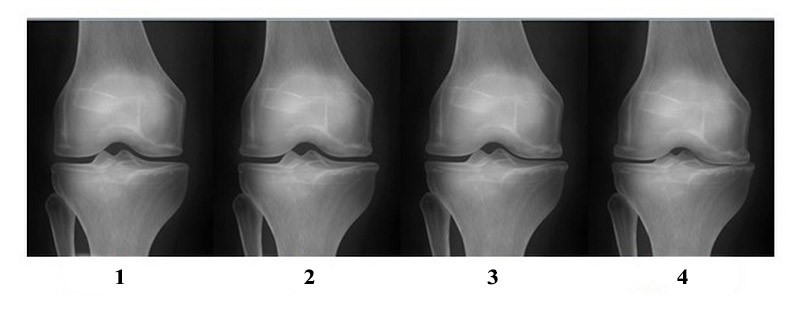

Важным параметром оценки субхондральной кости (СХК) является наличие остеосклероза – уплотнения в области суставной поверхности, на фоне которого параллельно появляются очаги истончения костного вещества. Клинико-рентгенологические критерии ОА наиболее полно разработаны для коленного сустава и включают классификации М. Лекена (1980), Дж. Келлгрена и Дж. Лоуренса (1957), А. Ларсена (1987), Н. С. Косинской (1961). Сегодня для определения стадии ОА традиционно используется классификация Дж. Келлгрена и Дж. Лоуренса (1957), усовершенствованный М. Лекеном (1982). По Дж. Келлгрену и Дж. Лоуренсу выделяют IV стадии заболевания.

Несколько слов о рентгенологических стадиях остеоартроза по J. Kellgren & J. Lawrence, принятых в далеком 1957 году, о них мы подробно писали в материале «Гонартроз - деформирующий артроз коленного сустава»

- 0 стадия – отсутствие рентгенологических признаков при наличии клинических проявлений (боль, локальное повышение температуры, припухлость после больших нагрузок);

- І стадия – сомнительная – незначительные остеофиты, сужения суставной щели не определяется или минимальное; (N.B. Формально, по последним протоколам диагностики и лечения остеоартрита, наличие остеофитов и сужение суставной щели в совокупности с клиническими проявлениями дает право ортопеду-травматологу поставить диагноз - остеоартрит)

- ІІ стадия – минимальная – небольшие остеофиты на краях суставных поверхностей, появление краевых костных разрастаний суставных поверхностей, определяется незначительное сужение суставной щели;

- ІІІ стадия – средняя (умеренные изменения) – умеренное сужение суставной щели (в большинстве случаев преобладает с медиальной стороны); множественные небольшие или умеренной выраженности остеофиты на краях суставных поверхностей; незначительный субхондральный остеосклероз, особенно ярко выраженный в месте наибольшего сужения суставной щели; небольшие деформации суставных поверхностей.

- ІV стадия – выраженная (выраженные изменения) – резко выраженное сужение суставной щели до полного отсутствия; множественные остеофиты; выраженный субхондральный остеосклероз; значительные деформации эпифизов костей, образующих сустав

Далее рассмотрим стадии ОА на примерах

Высота суставной щели сохранена, но, присутствие остеофита, в совокупности с клиническими проявлениями, дает право ортопеду-травматологу поставить диагноз – гонартроз 1-2 стадии

Суставная щель сохранена, но неравномерна с медиальной и латеральной стороны. Четко визуализируется остеофит